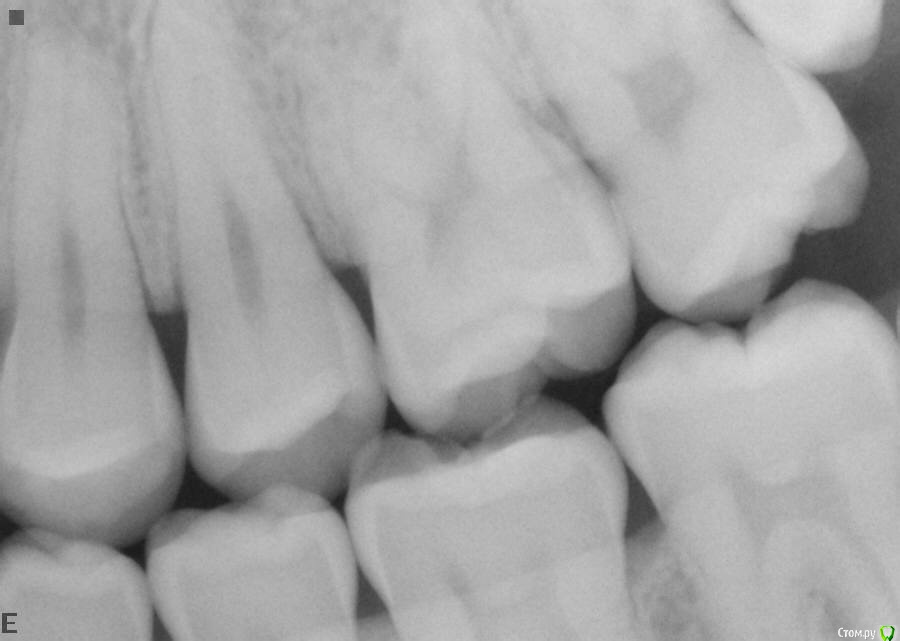

laz Опубликовано 31 мая, 2016 Поделиться Опубликовано 31 мая, 2016 Здравствуйте,Был на приеме у зубного врача, чтобы почистить зубы. Он сказал мне нужны пломбы на 4 зуба (1-7, 1-6, 2-7 2-6).Еще он сказал мне нужно удалить все зубы мудрости. (не обязательно сейчас, но в ближайщем будущем)Болей никаких у меня нет. Поэтому не знаю, как быть.Посмотрите, пожалуйста, на рентгены и очень хочу услышать Ваше мнение/совет.Заранее спасибо, Владимир. Ссылка на комментарий

red_butler Опубликовано 31 мая, 2016 Поделиться Опубликовано 31 мая, 2016 все правильно, удаляйте все восьмыеи девятый 5 Ссылка на комментарий